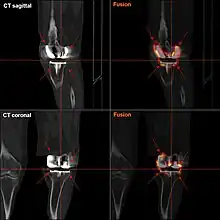

Loosening

Loosening of the prosthesis can be indicated on X-ray by thin radiolucent spaces around the implant, or more obviously by implant displacement.[55]